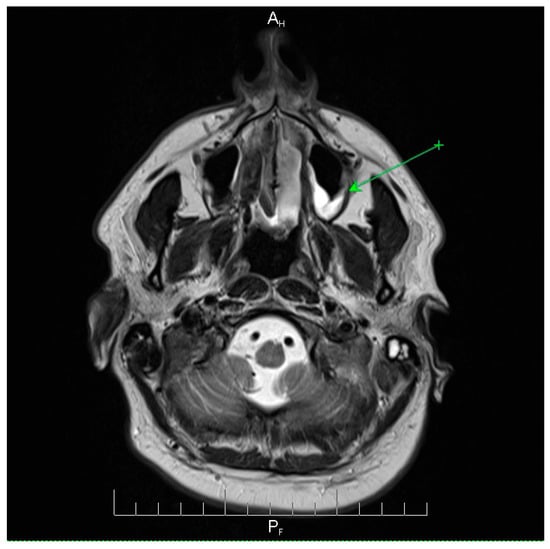

Fulminant Multidrug-Resistant Streptococcus pneumoniae Meningoencephalitis After Elective ENT Surgery: A Case Report

by Corina-Ioana Anton, Madalina Maria Zamfir, Alexandru Ghiță and Mihaela Raluca Mititelu

Pneumococcal meningoencephalitis is a severe infection associated with high morbidity and mortality. Although typically community-acquired, postoperative cases following elective ENT surgery are exceedingly rare. Antimicrobial resistance (AMR) among Streptococcus pneumoniae further complicates management, and missed opportunities for vaccination represent preventable risks. We report a case of a 41-year-old man with multiple comorbidities who developed fulminant S. pneumoniae meningitis 48 h after septoturbinoplasty. The clinical course was atypical, with altered consciousness but no classical meningeal signs, necessitating urgent intubation and intensive care admission. Cerebrospinal fluid cultures identified an MDR pneumococcal strain resistant to penicillin and macrolides but susceptible to vancomycin and meropenem. Empirical therapy with vancomycin and meropenem, combined with adjunctive corticosteroids and multidisciplinary ICU care, led to complete neurological recovery. This case highlights a rare but life-threatening postoperative complication and underscores two critical lessons. First, the growing challenge of multidrug-resistant pneumococcus requires timely recognition, aggressive empiric therapy, and access to effective agents. Second, the absence of pneumococcal vaccination in this high-risk surgical patient illustrates a preventable gap in care. Integrating vaccination screening into preoperative evaluations may reduce the risk of catastrophic postoperative CNS infections. Full article

Show Figures

Figure 1